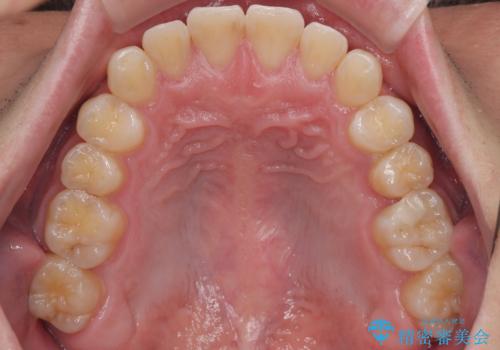

**前歯のデコボコ(叢生)**が整い、歯列全体が美しく改善

シザーズバイトの奥歯も正常なかみ合わせに改善

捻転歯も回転が修正され、全体的に清掃性・咀嚼効率が向上